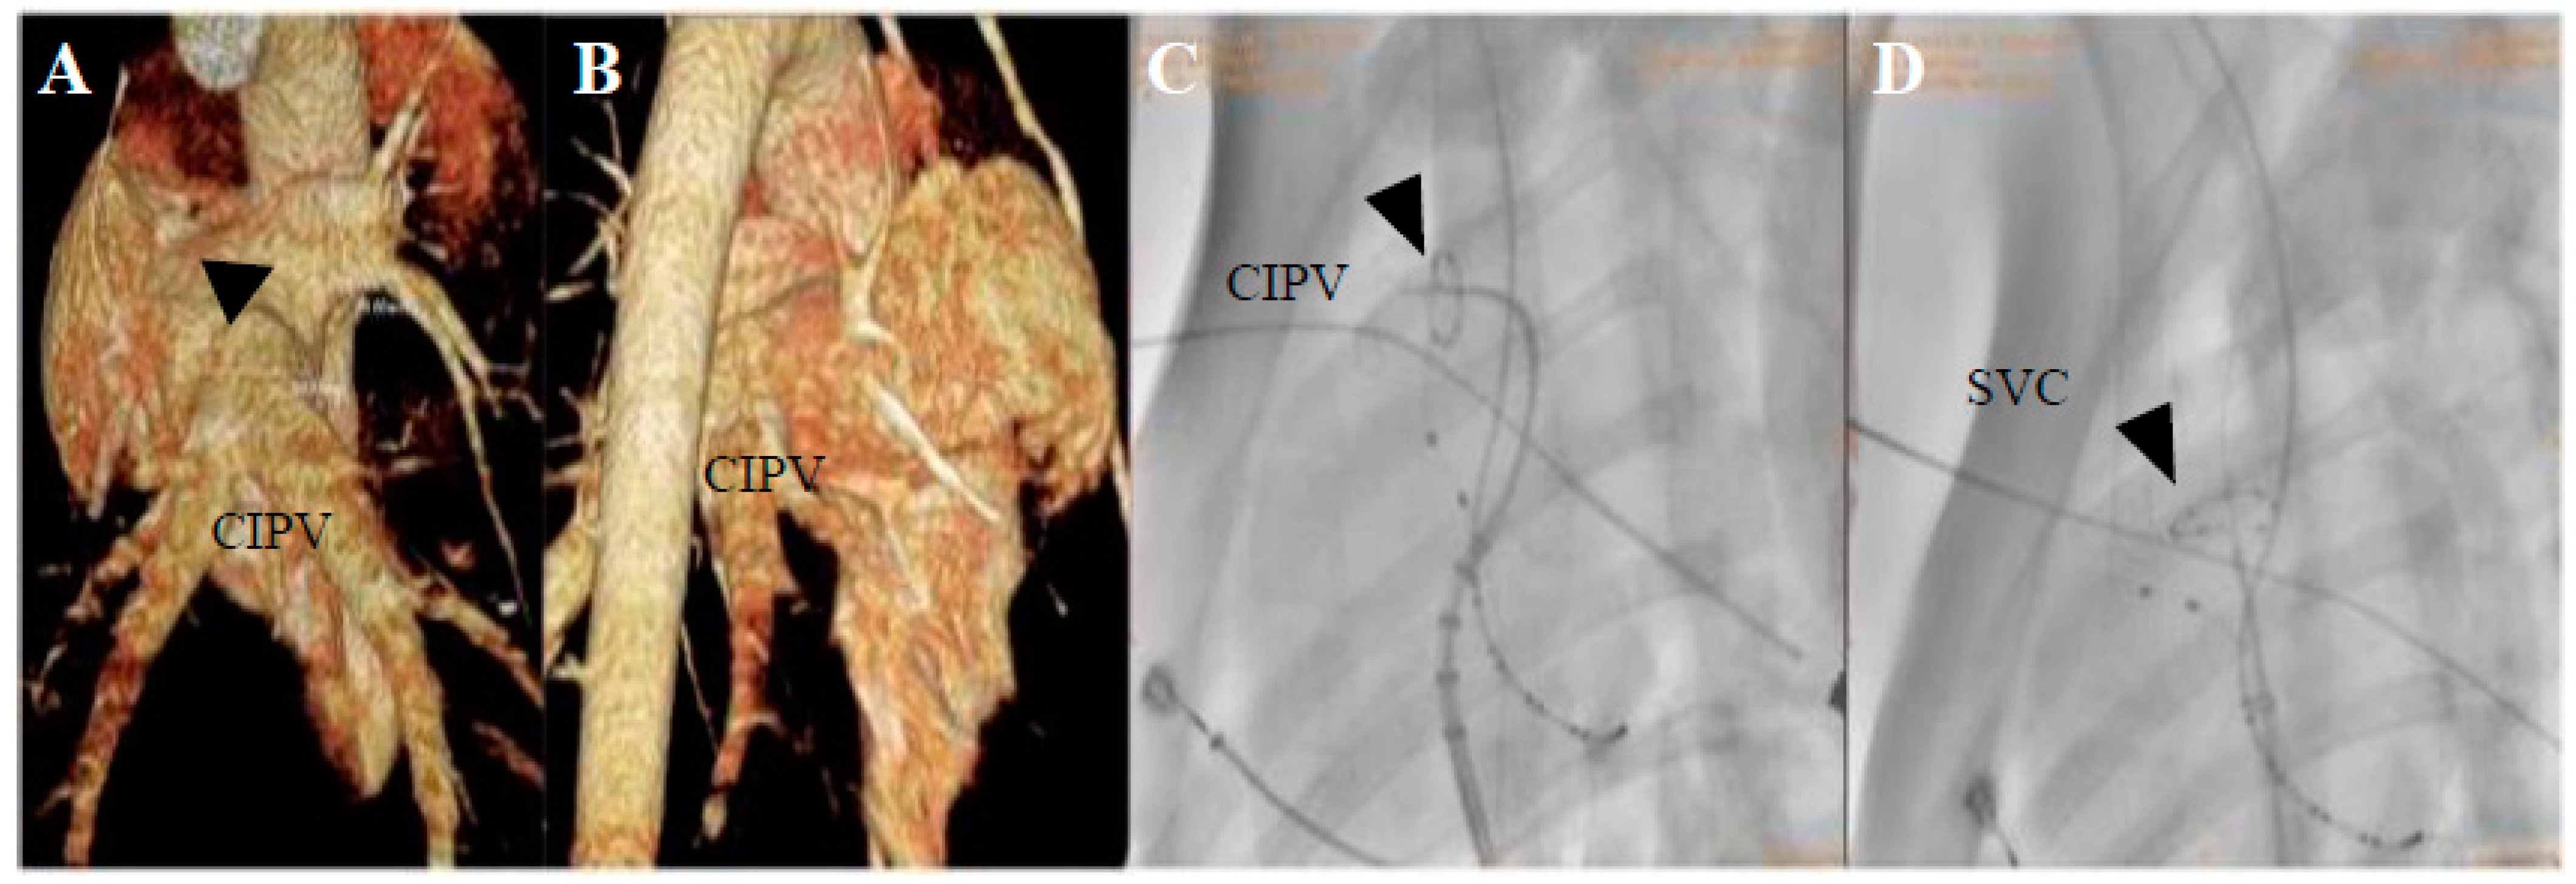

3.2. Electrogram, Voltage Mapping, and Complications